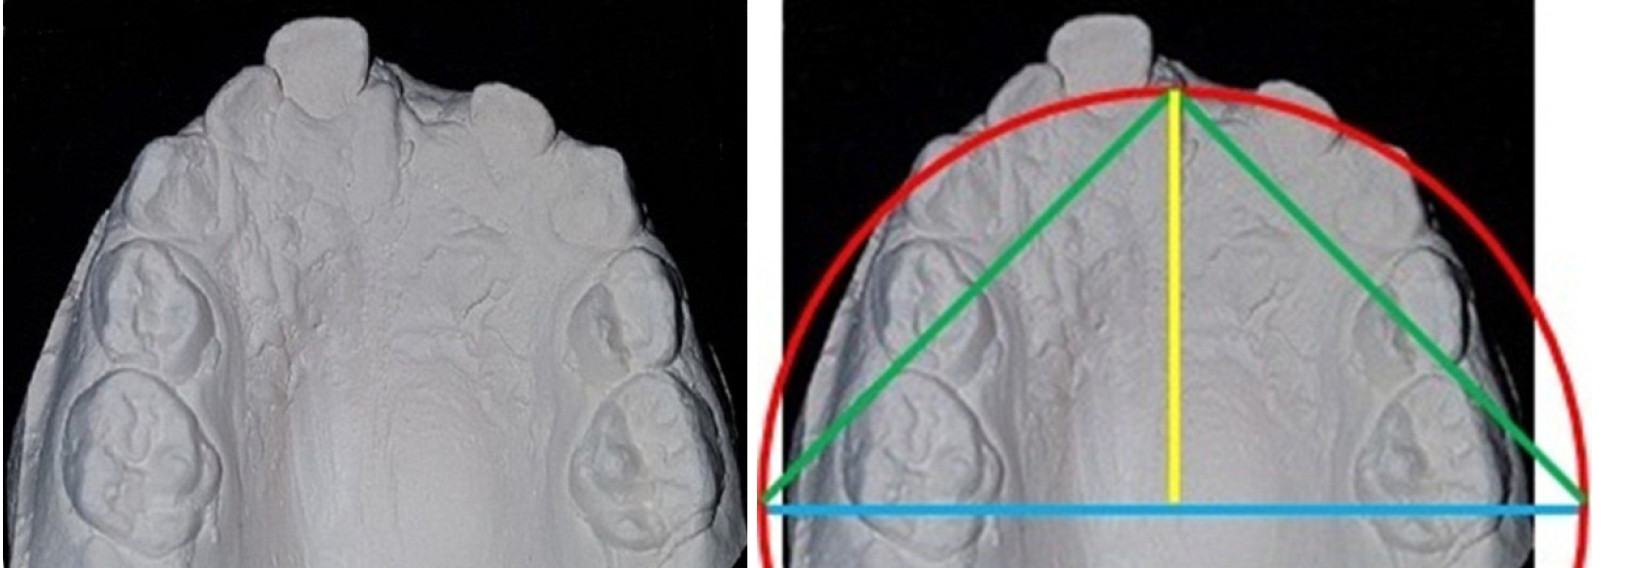

Полученные биометрические данные позволили нам разработать два метода определения трансверсальных размеров дуг по одонтометрическим показателям. В основе первого метода легли законы геометрии круга (прототип метода A. М. Schwarz) и расчет радиуса окружности по его длине (L = 2πR). Таким образом, к сумме коронок 10 молочных зубов добавлялась величина диастемной составляющей (в нашем случае 9 мм) и получалась длина полуокружности, которую достаточно было разделить на число π и получить величину радиуса окружности. Полученная величина, как правило, соответствовала глубине дуги и половине межмолярного расстояния. Полученные данные служили критерием оценки ширины зубной дуги и определяли величину ее сужения при аномалиях в трансверсальном направлении.

Второй метод основывался на расчете прогнозируемой величины резцово-молярной диагонали. Глубина дуги соответствует половине ее ширины, а эти размеры являются катетами прямоугольного треугольника с углами в 45 градусов, и их размер можно определить как произведение гипотенузы (резцово-молярной диагонали) к синусу угла в 45 градусов (0,707)

Таким образом, разработанные методы диагностики аномалий зубных дуг в трансверсальном направлении могут быть полезны врачам-ортодонтам, что представлено на клиническом примере. Полученные данные позволили сравнить размеры зубной дуги с прогнозируемой формой и ее графической репродукцией (рис. 1). При биометрии пациента 4 лет отмечалось сужение арки в области моляров и увеличение сагиттальных размеров, что подтверждено графическим построением арки и предполагаемым расположением центральной межрезцовой точки.